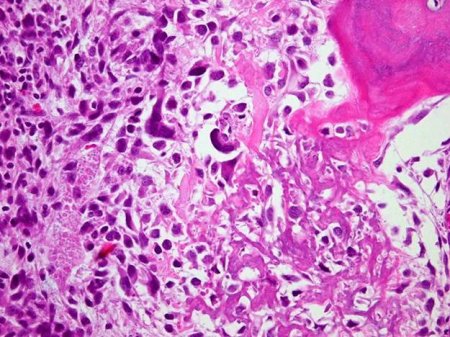

Osteossarcoma

Osteossarcoma osteoblástico; osteoide em forma de rede em estroma sarcomatoso altamente pleomórfico

Do acervo do Dr. Michael J. Klein e da Dra. Luminita Rezeanu